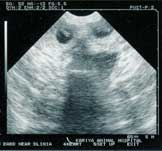

birth3.jpg<2002.02.05>赤ちゃんが出来た! エコー検査で2〜3頭いるようです。

birth3_1.jpg<2002.03.02>食欲旺盛、妊婦体型なのに太らない。なんと6匹もお腹にいるのが判明!